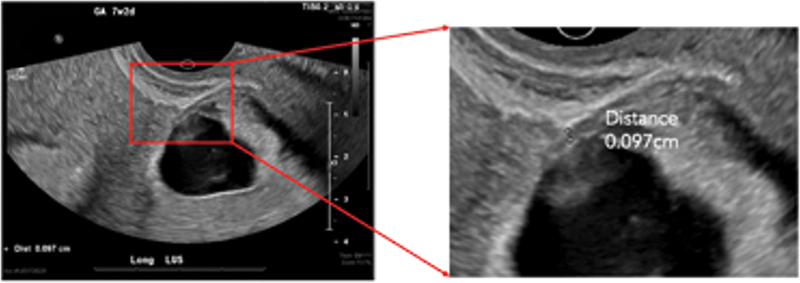

异位三胎妊娠、剖宫产瘢痕异位妊娠和子宫消融术后妊娠都是罕见的情况,会导致自然流产、宫内胎儿死亡、早产、胎盘异常和子宫破裂等重大疾病。一名 30 多岁的女性(G6P4014)曾做过子宫消融术,出现月经推迟和阴道点滴出血,造影显示两次宫内妊娠(其中一次有胎心活动),一次在剖宫产疤痕处活胎。医生对患者进行了广泛的咨询,让她了解自己和胎儿面临的风险,并讨论了各种治疗方案,包括预产期管理和终止妊娠。患者接受了不复杂的扩张刮宫术和双侧输卵管切除术,术后当天就出院回家,情况稳定。本病例强调了合并症的潜在复合效应,这些合并症会给咨询和管理带来困难。要点 接受子宫内膜消融术的患者应经过仔细挑选,并在高效避孕方面进行广泛咨询。许多情况都会对产妇的健康造成严重威胁,因此有必要讨论终止妊娠。

Heterotopic triplet pregnancy, cesarean scar ectopic pregnancy, and pregnancy following uterine ablation are all rare events that confer significant morbidity including spontaneous abortion, intrauterine fetal demise, preterm labor, abnormal placentation, and uterine rupture. A woman in her 30s, G6P4014, with a history of uterine ablation presented with delayed menses and vaginal spotting with imaging showing two intrauterine pregnancies (one with cardiac activity) and one live pregnancy at the cesarean scar. The patient was extensively counseled on risk to her and to the pregnancies; treatment options were discussed including expectant management and termination of pregnancy. The patient underwent an uncomplicated dilation and curettage with bilateral salpingectomy and was discharged home the day of the procedure in stable condition. This case highlights the potential compound effect of comorbid conditions that can pose difficulty in counseling and management. Key Points Patients undergoing endometrial ablation should be carefully selected and counseled extensively on highly effective contraception.Suspected cesarean scar pregnancies should be carefully evaluated early in gestation. Management should include thorough counseling and may be indivisualized.Many conditions pose a significant threat to maternal health and warrant a discussion of termination, which should be widely availaible and safe for all who need and/or desire it.